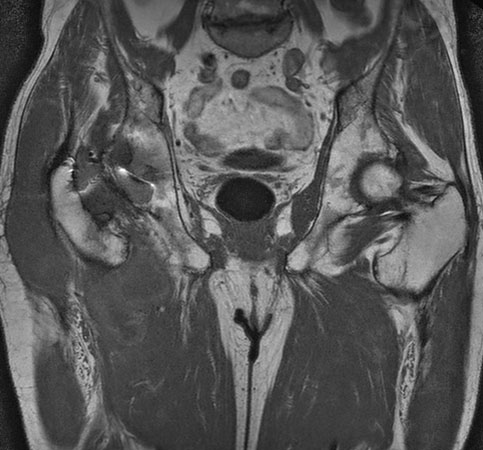

Hip imaging with metal implant using MARS at 1.5T

**Only for use with MR Safe or MR Conditional Implants by strictly following the Instructions for Use.